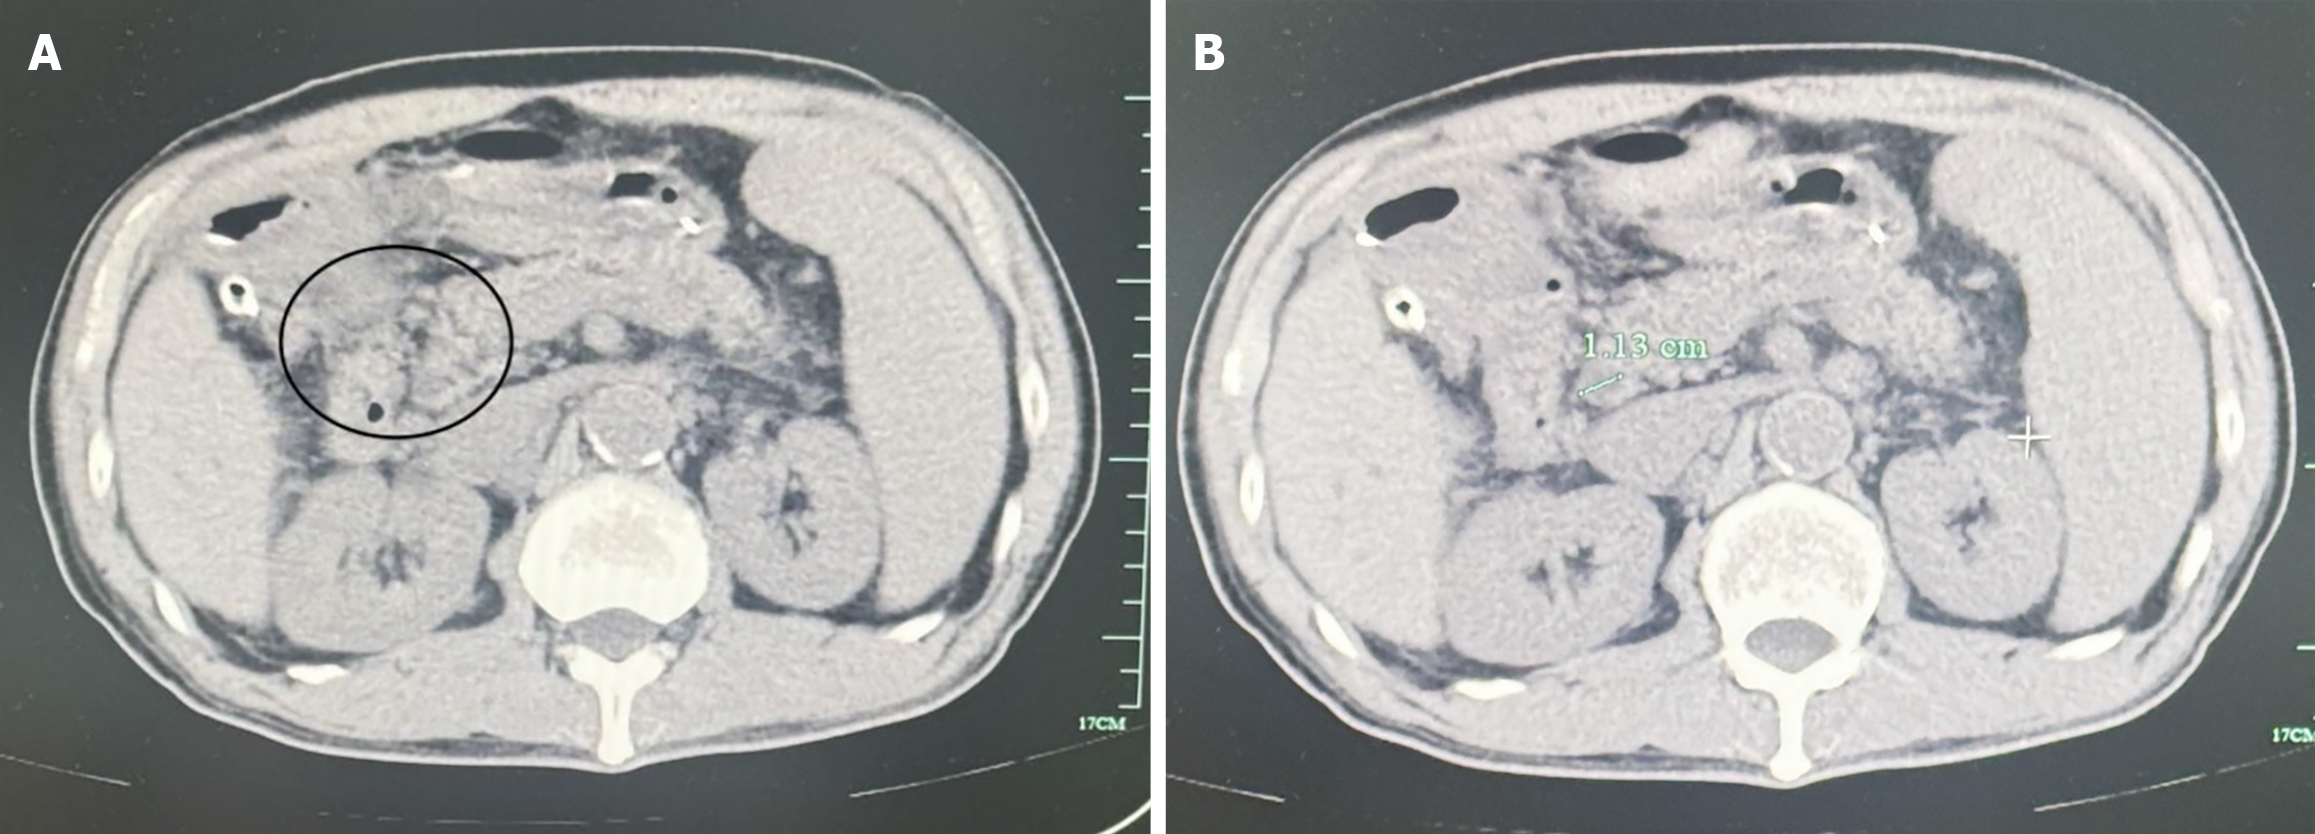

The surgical procedure was successful. Considering the prolonged duration of the biliary and intestinal interventions and severe intra-abdominal infection, the patient received comprehensive postoperative management, including fasting, intravenous antibiotic therapy, parenteral nutrition, and acid-suppressive treatment for gastric mucosal protection. On postoperative day 3, follow-up abdominal CT imaging revealed mild changes indicative of fluid leakage at the surgical site, albeit no significant abnormalities (Figure 3). The nasogastric and abdominal drainage tubes remained patent and functioned well, showing effective drainage. By postoperative day 8, enteral nutrition was initiated gradually. On postoperative day 20, the patient showed good tolerance to a liquid diet without any adverse symptoms. As the left abdominal drainage tube displayed no further output, it was subsequently removed. On postoperative day 23, the nasogastric tube was removed, and the patient reported no discomfort following its removal. A second follow-up CT scan performed on postoperative day 27 exhibited no notable abnormalities (Figure 4). The right-sided abdominal drainage tube was removed, and the patient was discharged on postoperative day 30. During his stay, no postoperative complications such as biliary or enteric fistula, gastrointestinal bleeding, or gastroparesis were observed. Histopathological examination of the excised gallbladder confirmed chronic cholecystitis, with localized areas of hemorrhage and necrosis of the gallbladder wall, along with the presence of mixed gallstones (Figure 5). The patient underwent structured follow-up every 6 months for 2 years postoperatively, including abdominal ultrasonography and hepatic function assessments. To reduce the risk of recurrence, a low-fat diet of < 40 g of fat per day was advised, along with an annual CT scan to evaluate the structural integrity of the repaired duodenal region. At the follow-up after 2 years of his discharge, the patient remained clinically stable. No abnormalities were detected in liver function tests, complete blood count, or other routine laboratory parameters. Abdominal CT imaging also demonstrated satisfactory recovery of the operative site, with no signs of recurrence or complications (Figure 6).

Figure 3

Figure 3 Postoperative abdominal computed tomography scan showing perisurgical exudation and dilatation of the common bile duct. A: Three days after surgery, a follow-up abdominal computed tomography (CT) scan showed slight exudation changes at the surgical site (within the circle); B: Three days after surgery, an abdominal CT scan revealed a dilated common bile duct with a diameter of approximately 1.13 cm.